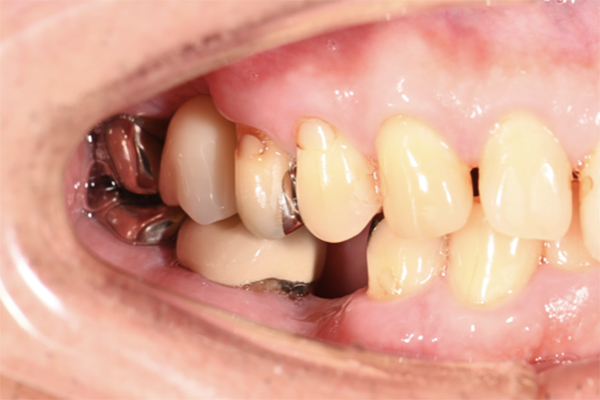

| 主訴 | 奥歯で噛めない、顎が痛い |

|---|---|

| 治療内容 | 奥歯のインプラント治療、前歯・奥歯の被せ物治療 |

| 治療期間 | 6ヶ月 |

| 治療費 | 350万円 |

| 治療リスク | 被せ物をつけた初期の段階で歯がしみることがある(時間とともに改善する) インプラント治療後に3日程度痛みと腫れを伴うことがある |